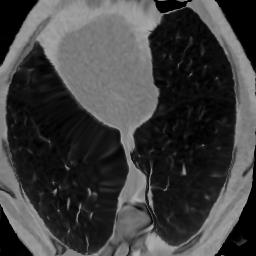

In clinical practice, well-aligned multi-modal images, such as Magnetic Resonance (MR) and Computed Tomography (CT), together can provide complementary information for image-guided therapies. Multi-modal image registration is essential for the accurate alignment of these multi-modal images. However, it remains a very challenging task due to complicated and unknown spatial correspondence between different modalities. In this paper, we propose a novel translation-based unsupervised deformable image registration approach to convert the multi-modal registration problem to a mono-modal one. Specifically, our approach incorporates a discriminator-free translation network to facilitate the training of the registration network and a patchwise contrastive loss to encourage the translation network to preserve object shapes. Furthermore, we propose to replace an adversarial loss, that is widely used in previous multi-modal image registration methods, with a pixel loss in order to integrate the output of translation into the target modality. This leads to an unsupervised method requiring no ground-truth deformation or pairs of aligned images for training. We evaluate four variants of our approach on the public Learn2Reg 2021 datasets \cite{hering2021learn2reg}. The experimental results demonstrate that the proposed architecture achieves state-of-the-art performance. Our code is available at https://github.com/heyblackC/DFMIR.